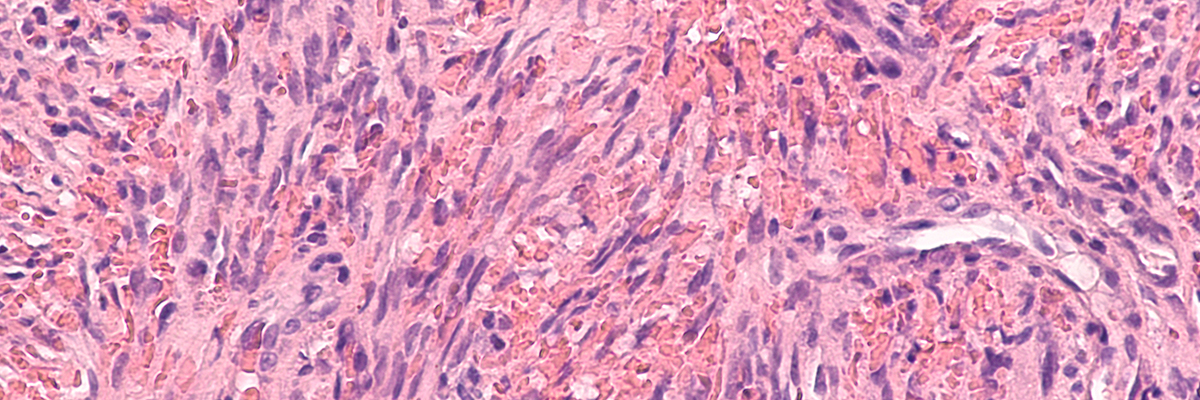

- Bone sarcomas

- Soft tissue sarcomas